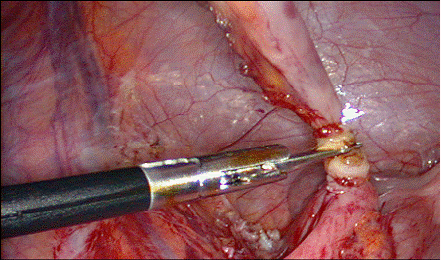

Se aplica o pensa atraumatica la nivelul varfului, dupa care se incepe disectia mezoapendicelui. Se pot folosi mai multe metode:

l daca mezoul este vizibil, nu este grasos sau inflamat si artera apendiculara se poate identifica, se creeaza o fereastra in mezou, deasupra ei si se aplica un clip pe vasele apendiculare, apoi se sectioneaza mezoapendicele; prin aceasta fereastra se poate introduce un fir neresorbabil pentru artera apendiculara, care se innoada intra - si extracorporeal; acest fir poate fi trecut si cu ajutorul unui ac;

Fig. 19 Aplicarea

clipurilor pe mezoapendice